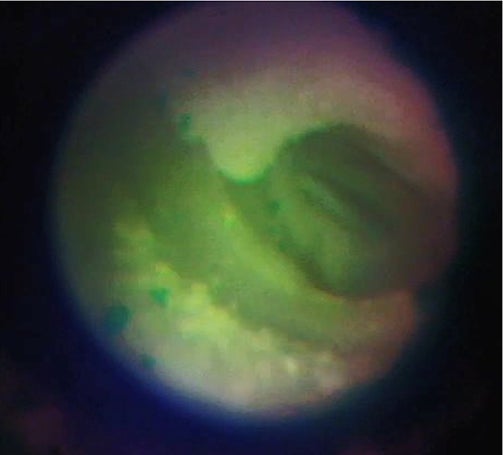

突発性難聴、顔面神経麻痺、外リンパ瘻といった疾患患者は本邦内で推計13.5万人にのぼる。これらの疾患においては、内耳や顔面神経の異常が原因となる。標準的な治療として内耳や神経の治療を目的とした全身ステロイド投与が行われる。効果がない場合には、鼓膜を小切開し、細径の内視鏡で病変部位(患部)を確認の上、薬剤を内耳や顔面神経に直接投与することで効果的な治療が期待される。

これまで既存の内視鏡を用いて同治療方法を試みたが、画像解像度の高い大径内視鏡では鼓膜切開が大きくなり、術後に鼓膜穿孔をきたすリスクがある。また、既存の極細径内視鏡を使用した場合には、画像解像度が低く、患部の確認が困難であった。Cellendo Scopeは細径と高解像度を兼ね備えており、当治療における患部観察に最適である。本年度の研究では、Cellendo Scopeを用い患部観察、薬剤投与を行い、薬効までの評価を目指す。

図6:鼓膜周辺模型のGI-POF極細内視鏡観察。左)外耳道からの内視鏡挿入、中)鼓膜小孔切開、右)鼓膜内観察